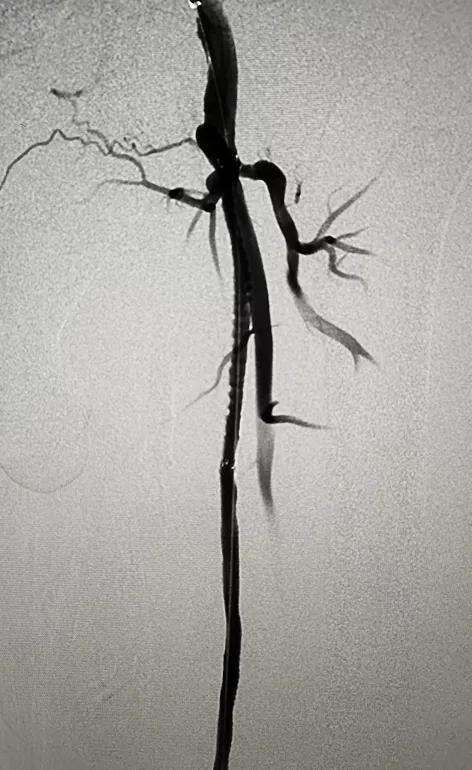

术前造影检查

血管外科主任程勇、副主任赵平带领团队在介入导管室为患者实施局麻下左下肢动脉造影+球囊扩张成形+支架植入术,成功为患者实施了下肢动脉硬化闭塞症微创治疗。